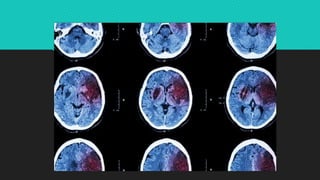

DIAGNÓSTICO

O diagnóstico do AVC é feito por meio de exames de

imagem, que permitem identificar a área do cérebro

afetada e o tipo do derrame cerebral. Tomografia

computadorizada de crânio é o método de imagem

mais utilizado para a avaliação inicial do AVC isquêmico

agudo, demonstrando sinais precoces de isquemia.

 Exames de Imagem:

 A tomografia computadorizada (TC) ou a ressonância nuclear

magnética (RNM) são fundamentais no diagnóstico.